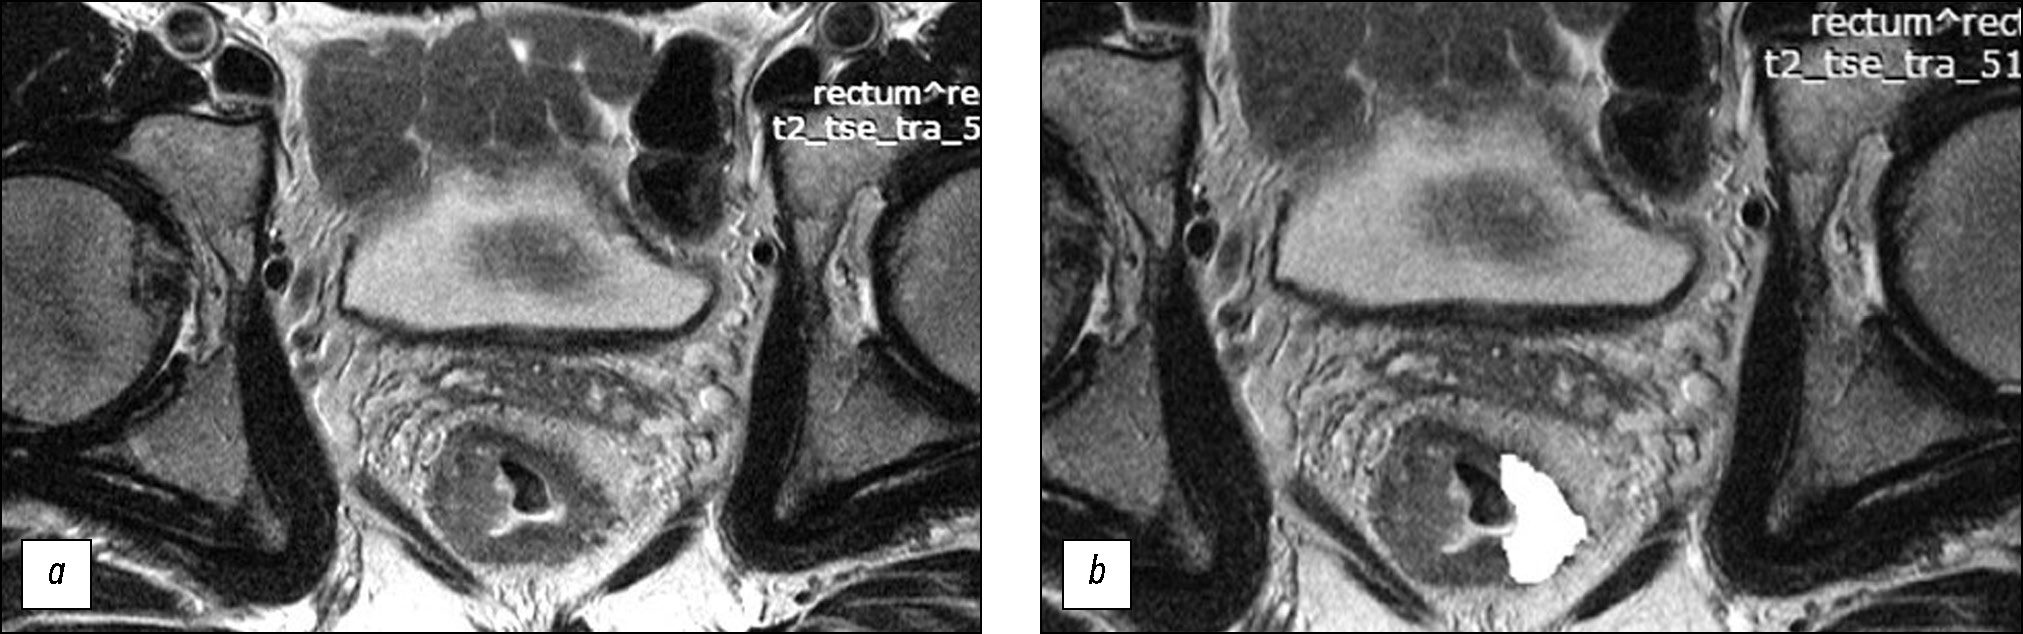

Анализ Т2-ВИ проводили ретроспективно, без информации о степени патоморфоза. Для расчёта параметров текстурного анализа врач-рентгенолог с 6-летним опытом абдоминальной визуализации отбирал первичное Т2-ВИ высокого разрешения на уровне центра опухоли и вручную выполнял 2D-сегментацию по наружному контуру опухоли, включая экстрамуральный компонент (рис. 1), после чего рассчитывались параметры текстуры второго порядка методом матрицы совместной встречаемости уровней серого (grey level co-occurrence matrices, GLCM) в компьютерной программе Mazdaver. 4.61. Отдельно лежащие опухолевые депозиты в область интереса не включали.

Рис. 1. Магнитно-резонансная томография малого таза, T2-ВИ, косо-аксиальный срез, опухоль нижнеампулярного отдела прямой кишки: a ― до неоадъювантной химиолучевой терапии; b ― после сегментации (белым цветом выделена область для автоматического расчёта параметров текстуры).